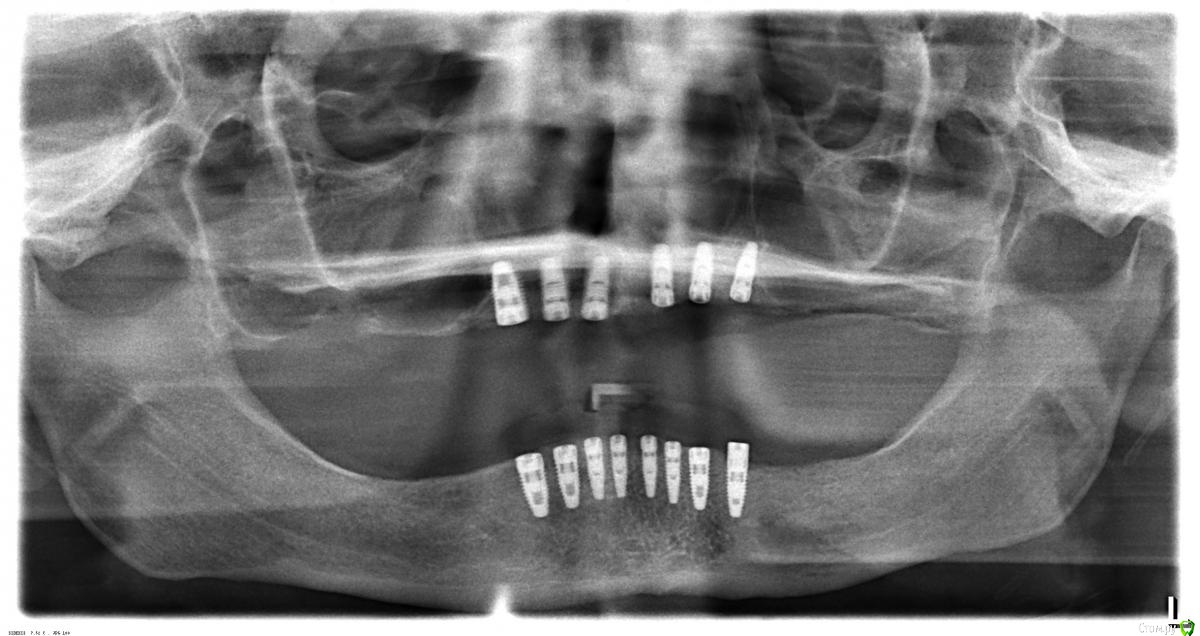

IvanK Опубликовано 9 октября, 2015 Поделиться Опубликовано 9 октября, 2015 Выложите панорамный снимок, Ссылка на комментарий

ivan.b88 Опубликовано 9 октября, 2015 Автор Поделиться Опубликовано 9 октября, 2015 Вот снимок. 2 Ссылка на комментарий

red_butler Опубликовано 9 октября, 2015 Поделиться Опубликовано 9 октября, 2015 Скажите а какая конструкция планировалась изначально, особенно интересно про нижнюю челюсть 1 1 Ссылка на комментарий

ivan.b88 Опубликовано 9 октября, 2015 Автор Поделиться Опубликовано 9 октября, 2015 Изначально планировалось, что на каждый имплант будут ставить отдельную коронку, за исключением верхних резцов (там на каждом импланте будет сдвоенная коронка). Мне хотелось бы, чтобы так и было. 2 Ссылка на комментарий